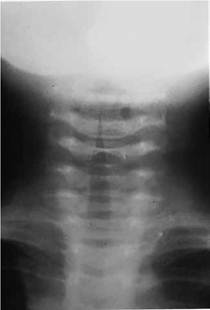

En la LT no complicada no es aconsejable realizar estudios de laboratorio y gabinete por ser su diagnóstico básicamente clínico.6,17 Por ello, la evaluación radiológica no es necesaria y solo debe ser considerada en situaciones específicas: a) en un niño con síntomas atípicos; b) si el diagnóstico no es claro; c) ante la sospecha de aspiración de cuerpo extraño; y d) cuando la respuesta al tratamiento usual no es satisfactoria.22 Cuando se realiza una radiografía anteroposterior de cuello, la imagen característica de la LT es una sombra o estrechamiento de la tráquea en el área subglótica (signo de “la aguja, en reloj de arena o del campanario”) de 5 a 10 mm que confirma el diagnóstico (figura 2). En la proyección lateral o de perfil del cuello puede observarse una sobre distensión de la hipofaringe y un estrechamiento por debajo de las cuerdas vocales que ayuda a descartar epiglotitis, absceso retrofaríngeo y aspiración de cuerpo extraño (figura 3). Cuando se realizan los estudios radiológicos, el niño debe ser monitorizado de cerca por un personal con habilidades y experiencia en el manejo de vías aérea difícil. Sin embargo, su realización se halla contraindicada cuando hay signos de obstrucción inminente.11,25 El valor diagnóstico de estos hallazgos radiográficos es cuestionable, porque no se observan en todos los casos de LT viral y se ha demostrado que su sensibilidad y especificidad son muy bajas para confirmar o descartar esta enfermedad.11

Figura 3. Sobredistensión de la hipofaringe